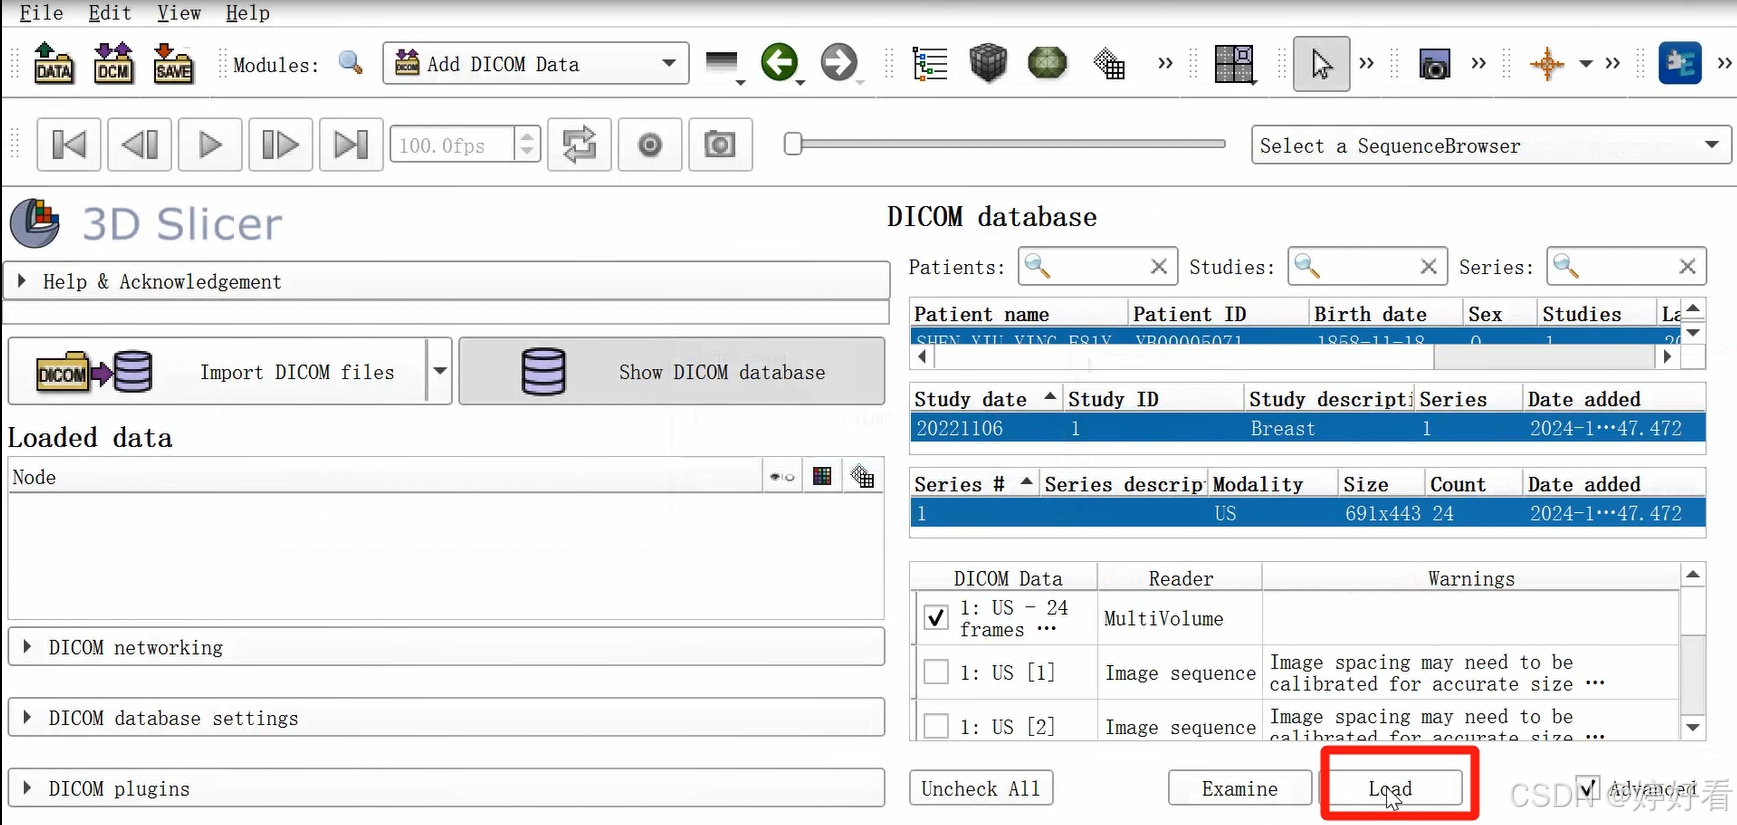

1.2 选中Patient name,然后依次点击Examine-Load,这样图片就打开了。